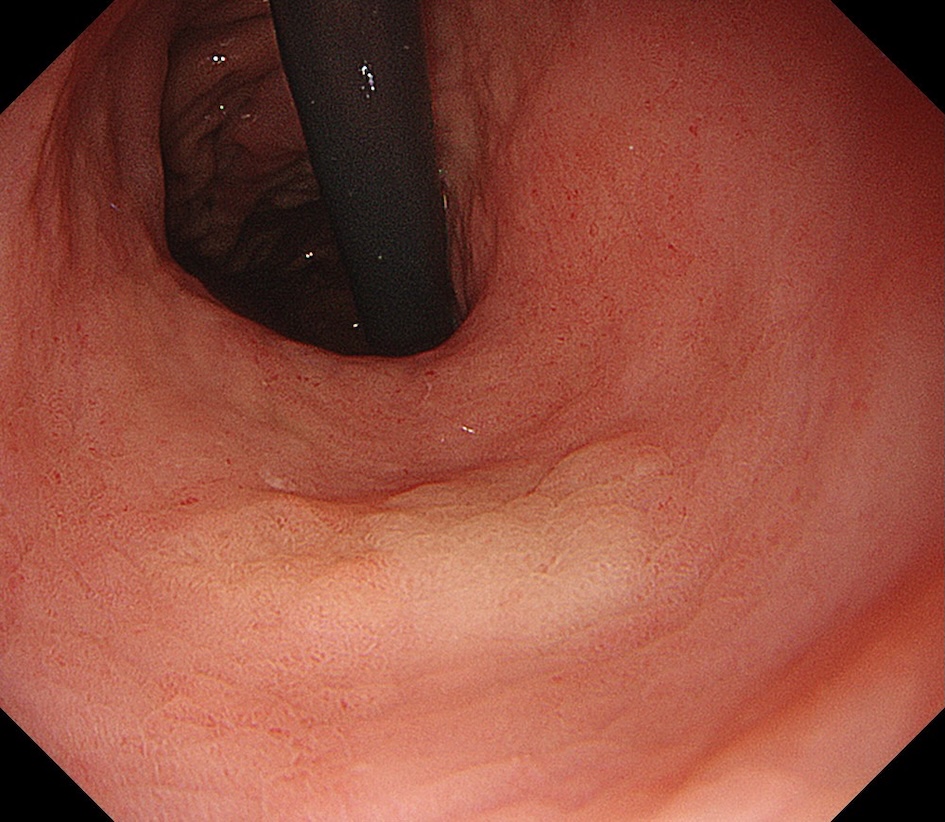

• 白色光観察②(近景)

強調設定:B8

図2

白色光観察:反転し近接観察すると、病変は褪色調を呈する平坦隆起型(0-Ⅱa)病変として認識される。病変左側(前壁側)の一部に淡い発赤を認める。